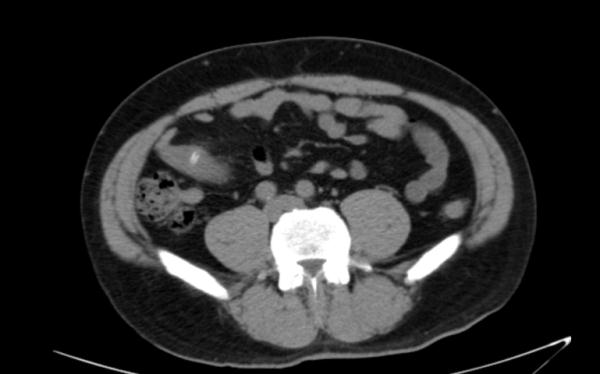

患者在1周前吃八宝粥时误呑了一粒枣核,后出现右侧腹痛,疼痛逐渐加重。来院就诊时已经出现腹膜炎的表现,腹部CT提示右侧腹小肠内异物,经普外科医生会诊后,考虑肠内异物继发小肠穿孔,需要立即进行手术。手术中,普外科医生用腹腔镜探查患者腹部,明确小肠异物为枣核,且枣核已经导致小肠系膜侧及对侧肠壁双侧穿孔,伴有小肠系膜内脓肿形成。